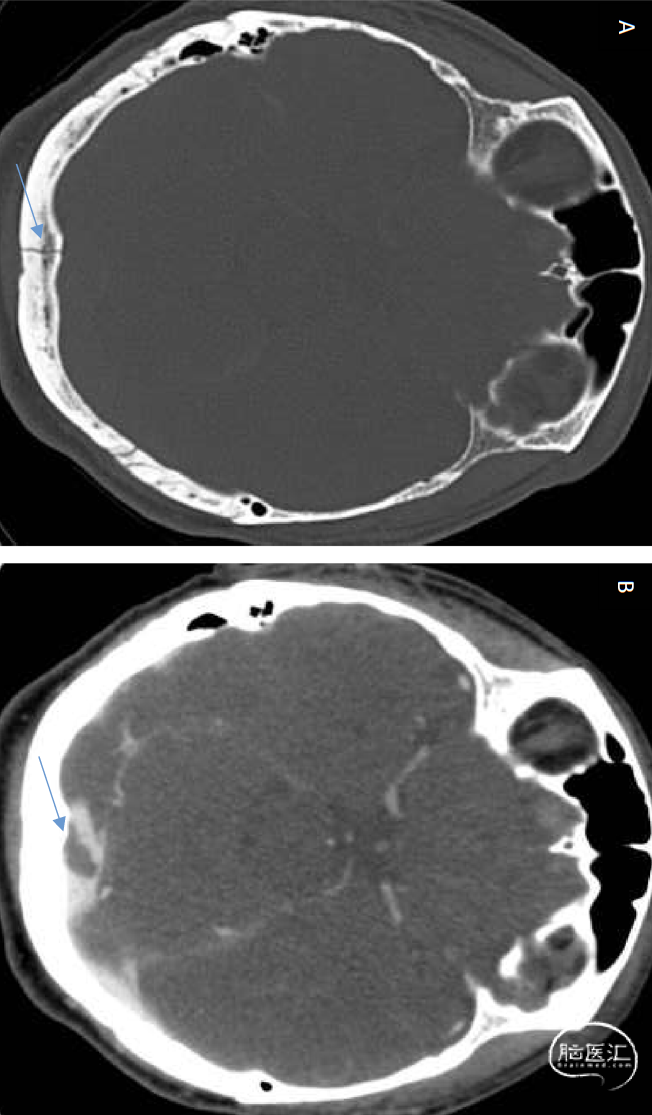

图2(A)轴位CT(骨窗)显示枕骨中线骨折贯穿窦汇(箭头所示)。(B)轴位CT静脉造影(CTV)可见窦汇处脑静脉窦血栓形成(箭头所示),正位于骨折部位上方。该病例经资深专家确认,展示了窦汇直接创伤继发血栓形成的典型表现: